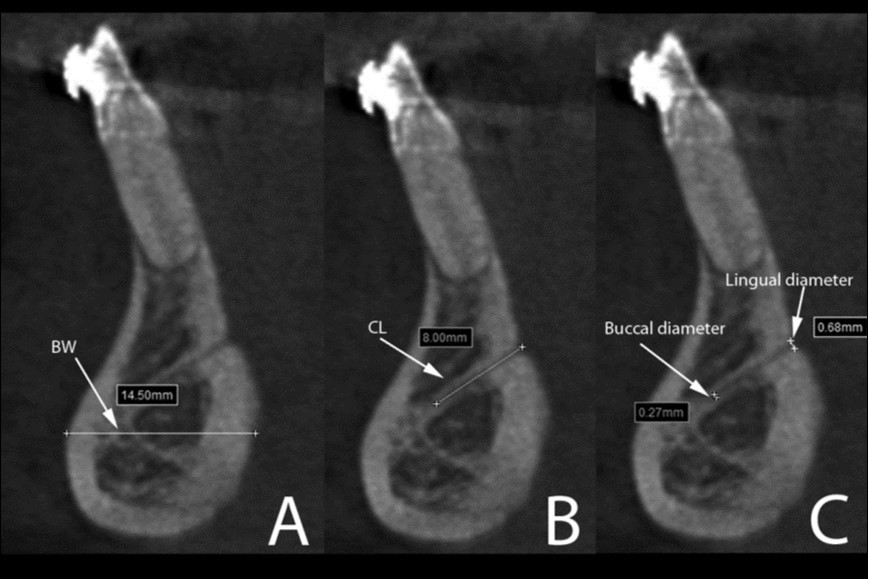

Human, Chimpanzee and Gorilla groups showed significant differences in the dimensions of the mandibular canal, mental foramen, incisive canal, lingual canal and in the anterior mandibular bone width (Figure 4). The Gorilla group showed significant higher medians for the mandibular canal, lingual canal length and bone width than Human and Chimpanzee groups (Table 1).

Figure 4.Cross-sectional views show the lingual canal. Images (A), (B) and (C) show the measurement of bone width (BW, the longest distance in the anterior mandibles under the lingual canal), canal length (CL) and lingual canal diameter (buccal and lingual), respectively.

On the other hand, human mandibles showed significant larger range of mental foramen (3.3mm/2.7-4.0mm) compared to Chimpanzee (2.1mm/1.7-2.7mm) and Gorilla (2.1mm/1.9-2.9mm). No incisive canal could be observed in the Gorilla group, while very few were presented in Chimpanzee. The incisive canal diameter was significantly larger in Human (IC/start: 1.9mm/1.6-2.6mm) than in Chimpanzee (IC/start: 0.9mm/0.8-1.1mm). For the root lengths, the longest third molar was observed in the Gorilla group (13mm/10.1-14.8mm), whereas the Human group presented the longest second premolar (14.5mm/13.4-16.4mm) and Chimpanzee showed the longest canine (18.1mm/15.4-21.9mm).